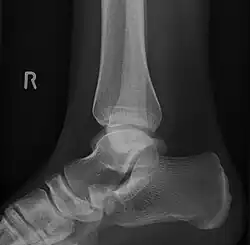

Lateral projection of type 2 -